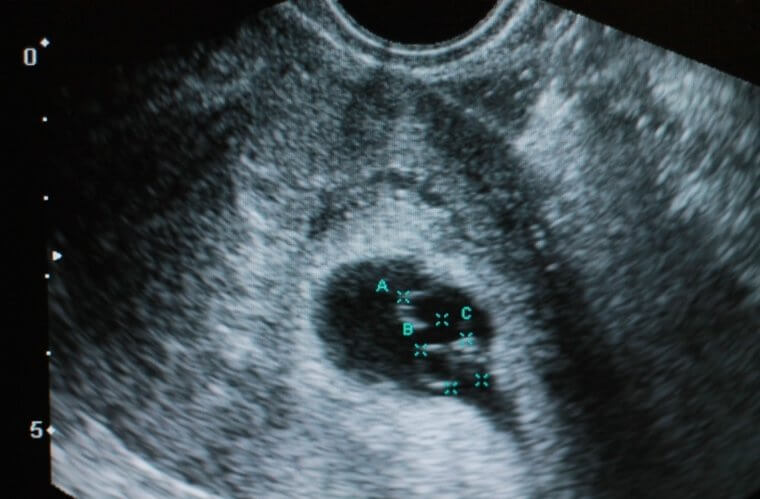

As the days passed, Angie and Gino talked about all of the possibilities. They both hoped they could give their two sons a sister and finally complete their little family. The closer it got to the day when they'd go to the doctor and learn what they were having, the more excited the couple got. When the time did come, and they went in for the ultrasound, they finally got the news they'd been waiting for.

The doctor told them that they were going to be proud parents to a new daughter. The two were incredibly happy. However, that's not the only thing that the doctor told them.

As you might imagine, Angie and Gino were caught off guard by news of the triplets, but what the doctor said next made the announcement even more special. The doctor informed them that two of the little girls shared one placenta while the third shared another. Basically, this meant that they were having identical twins, in addition to another daughter. This wasn't just a typical case of triplets, which by itself is rare.

When Angie was only around 26 weeks into the pregnancy, she started to feel like something wasn't right. She told her husband, and the two wasted no time getting to the hospital. It turned out that she was right and that Baby B, as the hospital called her, had liquid levels that were too low. At the same time, Baby C's liquid levels were too high. It was a serious issue.